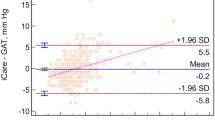

Scatter plots of SSI against AST are shown in Fig. 3. There was no significant association between SSI and AST in total, CSCR, or non-CSCR group (p = 0.21, 0.31, 0.12 for superior AST; p = 0.11, 0.69, 0.36 for temporal AST; p = 0.61, 0.37, 0.37 for inferior AST; p = 0.63, 0.87, 0.77 for nasal AST, respectively; linear mixed models).